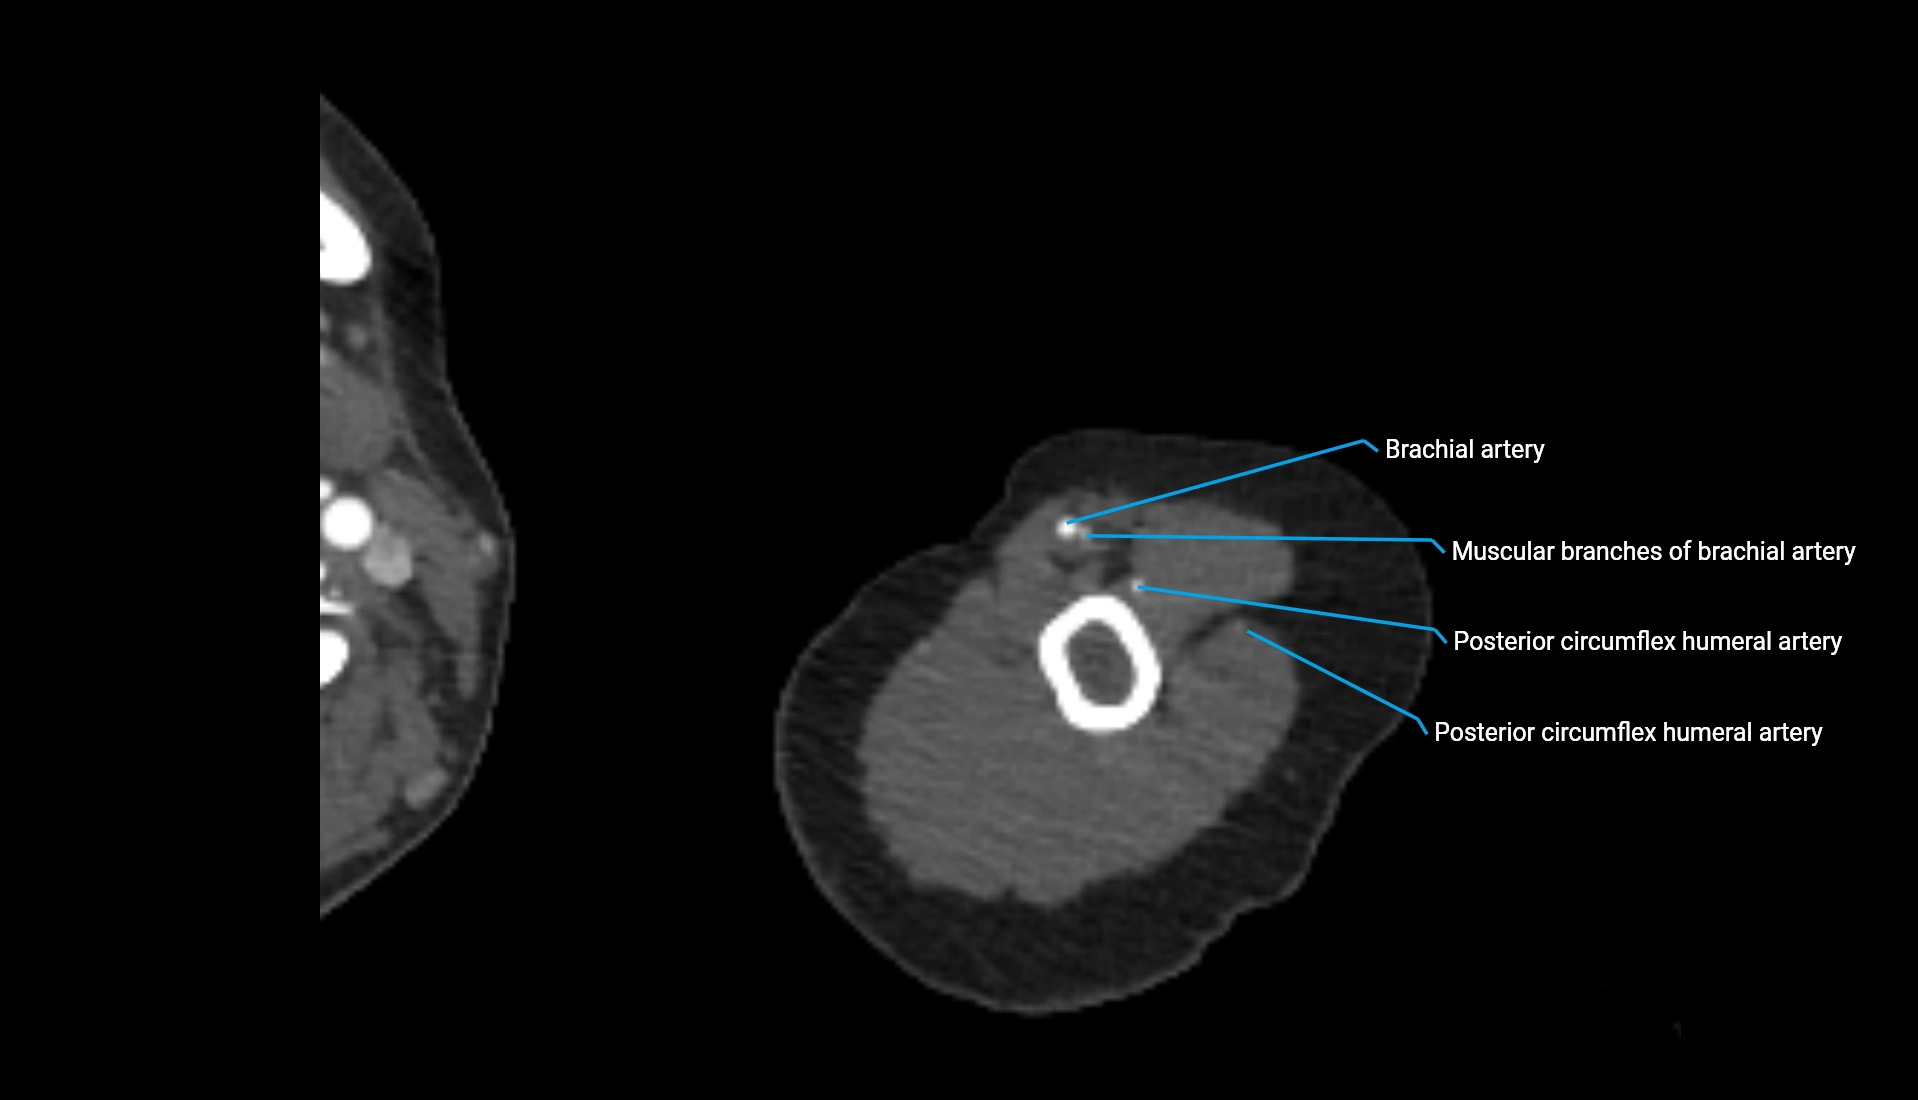

CT Appearance

Non-Contrast CT:

• Cortex: High-density, sharply defined

• Subchondral bone: Dense cancellous matrix

• Articular surface: Smooth concave contour articulating with the capitellum

• Excellent for evaluating bone integrity, alignment, and subtle fractures